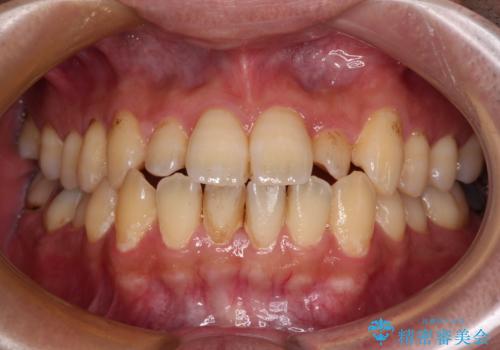

海外勤務中のインビザラインによる矯正治療

- 前歯のクロスバイトを気にして来院され患者様です。

定期的に日本には帰国するものの、日ごろは海外でお仕事をされているとのことで、インビザラインによる治療を希望されました。

トラブルが起こった時に対応ができない、来院を帰国のタイミングに合わせなければならないため治療が長期化するなど困難はありますが、ワイヤー矯正と比べると治療を進めやすいといったメリットがあるので、インビザラインにて矯正治療を行うこととしました。

治療期間が世界的な感染症の流行時期と重なったため、海外と日本での往来が困難となり、治療継続が懸念されました。

それでも、しっかりとマウスピースを装着してくださったので、大きなトラブルもなく治療を終えることができました。